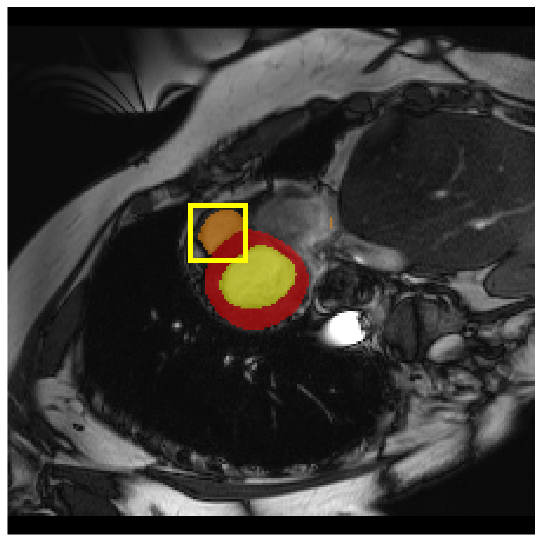

4.3.2 Visual Comparisons

Visualization of our method on the Synapse and ACDC datasets is shown in Fig. 3(a) and Fig. 3(b). For the Synapse dataset illustrated in Fig. 3(a), FCT failed to accurately segment SM and GB, while MERIT achieved precise segmentation of SM but struggled with GB. In contrast, our method achieved accurate segmentation of both SM and GB. Regarding the ACDC dataset shown in Fig. 3(b), while previous methods achieve comparable segmentation of the Myo and LV to the GT, they exhibit noticeable errors on the RV, including invasion into adjacent organs and misrecognition. On the other hand, our method accurately segments across all three structures Myo, LV, and RV, performing as precisely as the GT. We demonstrate the superiority of our method quantitatively and qualitatively.